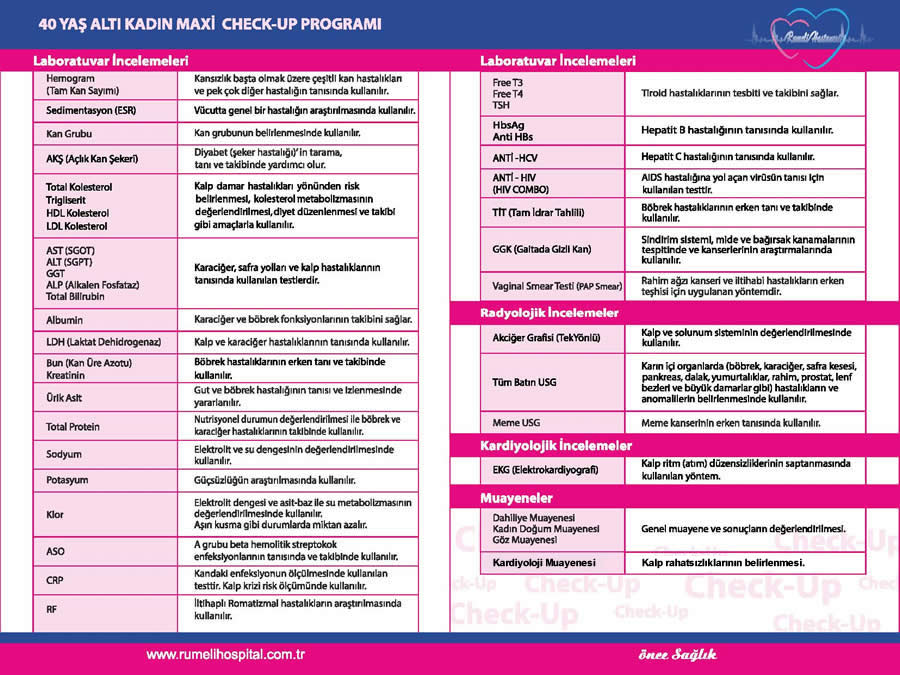

Kadin Check Up Programlari Hakkinda Bilinmesi Gerekenler Acibadem

Check Up Erken Teshis Hayat Kurtarir Ozel Rumeli Hastanesi

Check Up Erken Teshis Hayat Kurtarir Ozel Rumeli Hastanesi